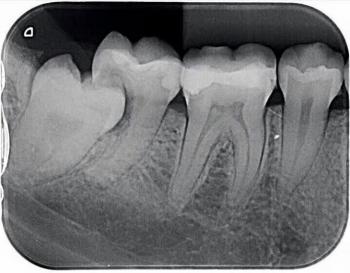

The Foundation: Surgeons remove one of the patient's teeth—often a canine—along with a portion of the surrounding jawbone and ligament. This tooth-bone unit is then meticulously sculpted and a tiny, custom optical lens is inserted into its center.

The Window to the World: This "tooth-lens" complex is then implanted into the eye. Over time, the body’s own tissues integrate with the tooth and bone, creating a stable, living framework that holds the new lens securely in place. Because the tooth is made of the patient's own tissue, the body does not reject it—a common problem with artificial implants.

Structural Integrity: Teeth are the hardest substances in the human body. They are designed to withstand a lifetime of incredible force, making them a surprisingly durable anchor.

The Power of the Ligament: The periodontal ligament that holds your tooth in your jaw is a unique tissue with a rich blood supply. This is key to the success of the OOKP procedure, as it promotes healing and integration with the eye tissue.